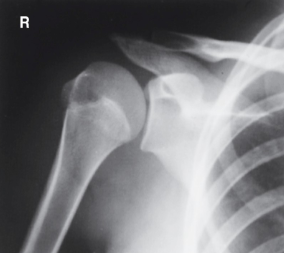

is this a normal or dislocated shoulder? in which direction is it dislocated?

dislocated, anterior